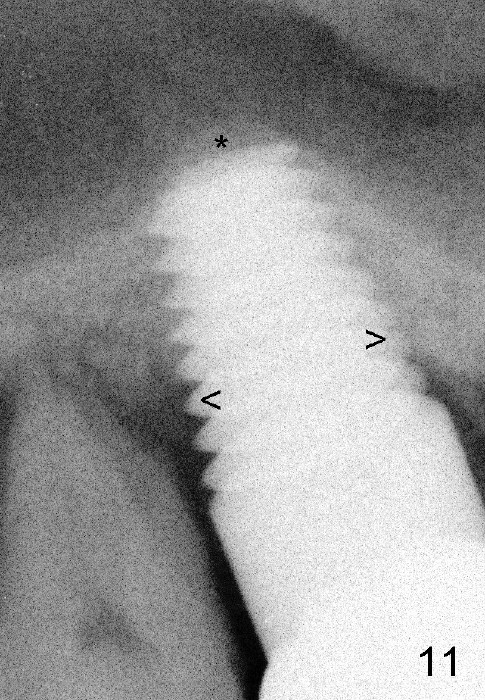

Six months post cementation, the patient returns for follow-up with chief complaint of food impaction between the upper right last 2 teeth. It is difficult to remove. The distal 2nd thread appears not to be covered by the bone, whereas the mesial one is (compare Fig.11 arrowheads). *: sinus lift.